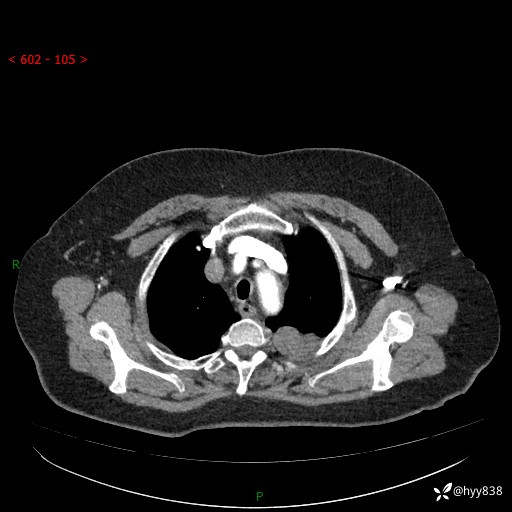

简要病史:患者于8年前体检行胸部CT检查发现左上肺结节(4mm),患者平素间断咳嗽咳痰,无心慌、胸闷、胸痛、呼吸困难、低热、盗汗,无头痛、头晕,无腹痛、腹胀等不适,未行特殊处理,定期复查。2023-09-21胸部CT示左上肺结节(2cm)较前增大,2024-02-01胸部CT示左上肺尖后段(39*32mm),左侧肺门及纵隔淋巴结增大,现患者欲求手术治疗,遂来我院就诊,以“左上肺结节”收入我科。 患者自起病以来,精神可,睡眠可,饮食可,大小便正常,体重无明显改变。

增强(动脉期+静脉期)